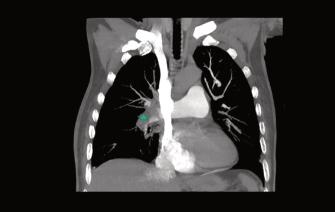

COVID-19sehaasociadoaunaumentodefenó‐menostromboembólicos.Esteaumentodela pro-coagulabilidadvascularpuededeberseaun efectodirectodelvirussobreelendotelio,produ‐ciendounainflamaciónendotelialdifusa.La Angiotomografíatorácicaconcortesfinosesel métodoparavalorarsimultáneamenteelinters‐ticiopulmonar,asícomotambiénelprobable compromisovascularquesedebenidentificar enlosestadiosmástempranosposibles(Fig.2)